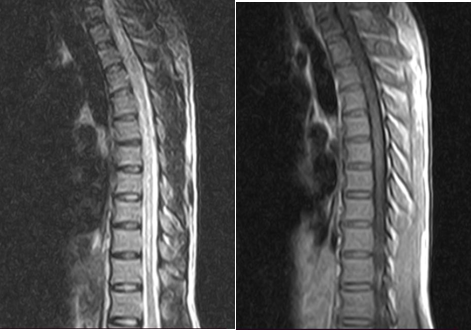

Glasgow coma scale (GCS) was E4M6V5 15/15, well-oriented in time and space, pupils were bilaterally equal round and reactive to light, plantars were extensors bilaterally. On sensory exam, sensory level was found at the level of T10. Motor examination showed normal bulk and tone, power was 5/5 (MRC grade 5) in upper limbs and 1/5 (MRC grade 1) in lower limbs and deep tendon reflexes were 3+ in all limbs. No cerebellar signs in upper limbs but could not be assessed in lower limbs due to decrease in motor power. Rest of the exam was unremarkable (Table 1 & 2) (Figure 1).

Figure 1 MRI Dorso lumbar spine with contrast (A) T2 SAGGITAL view (B) T1 SAGGITAL view.

Suspicion of transverse myelitis was made; lumbar puncture was done and CSF was analyzed for routine examination and oligoclonal bands. The result showed pleocytosis, predominantly neutrophils but with normal protein and glucose. Oligoclonal bands were positive. MRI cervicodorsal spine with contrast was also done; the sagittal view showed subtle area of hyperintense signal at distal thoracic cord, more conspicuous T3 to T7. Taken the results of CSF studies and MRI cervicodorsal spine, all features strongly suggested longitudinally extensive transverse myelitis. The patient was then started on pulse dose steroids; Inj. Methylprednisolone for 5 days. Patient’s power of lower limbs gradually improved to 4/5 on MRC scale and was later discharged to home.